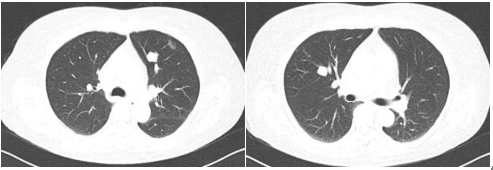

胸部低剂量CT(2020年9月):双肺多发大小不等的结节灶,最大者长径约1.9cm,考虑为转移瘤可能。

图示:胸部低剂量CT(2020年9月)